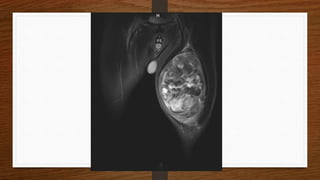

• Paciente carece de informe médico ya que por la complejidad del estudio es

necesario dar un diagnóstico certero es necesario disponer de otros estudios

que permitan conocer la etiología del tumor, los estudios realizados se limitan

a un ecografía y una RM simple, es imprescindible para un mejor diagnostico

en este tipo de casos realizar una RM contrastada ya que nos permitirá

diferenciar las áreas necróticas de mejor manera así como vascularización

• Paciente carecede informe médico ya que por la complejidad del estudio es necesario dar un diagnóstico certero es necesario disponer de otros estudios que permitan conocer la etiología del tumor, los estudios realizados se limitan a un ecografía y una RM simple, es imprescindible para un mejor diagnostico en este tipo de casos realizar una RM contrastada ya que nos permitirá diferenciar las áreas necróticas de mejor manera así como vascularización